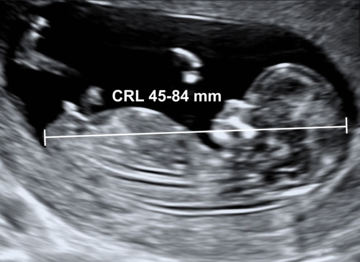

Diagnóstico ultrassonográfico:

- Diagnóstico de espinha bífida requer exame sistemático de cada arco neural, desde a região cervical até sacral, tanto no corte transversal como longitudinal. No corte transverso, o arco neural normal aparece como um círculo fechado com pele íntegra cobrindo, enquanto que nos casos de espinha bífida, o arco tem forma de U e há meningocele abaulada adjacente (cisto de parede fina) ou mielomenigocele. A extensão da lesão e de qualquer cifoescoliose associada é melhor avaliada no corte sagital.

- Localização da espinha bífida aberta: lombossacral (65%), sacral (24%), toracolombar (10%), cervical (1%).

- Espinha bífida aberta é associada à Malformação de Arnold-Chiari II com deslocamento caudal do tronco cerebral (brain stem – BS) e obliteração da cisterna magna.

- Com 11-13 semanas, no corte sagital médio da cabeça, a parte inferior do cérebro entre o osso esfenoide anteriormente e o osso occipital (occipital bone – OB) posteriormente, pode ser dividida em tronco cerebral anteriormente e uma combinação de 4o ventrículo e cisterna magna posteriormente. Na maioria dos casos, o diâmetro do tronco está aumentado, a distância entre o tronco e o osso occipital (“BSOB”) está diminuída e a razão BS/BSOB é >1.0 .

- No segundo trimestre, mais de 95% dos fetos apresentam acavalgamento dos ossos frontais ( sinal do limão) e obliteração da cisterna magna com “ausência” de cerebelo ou curvatura anormal dos hemisférios cerebelares ( sinal da banana). Grau variável de dilatação ventricular está presente em todos os casos de espinha bífida ao nascimento, mas em apenas 70% dos casos no segundo trimestre.